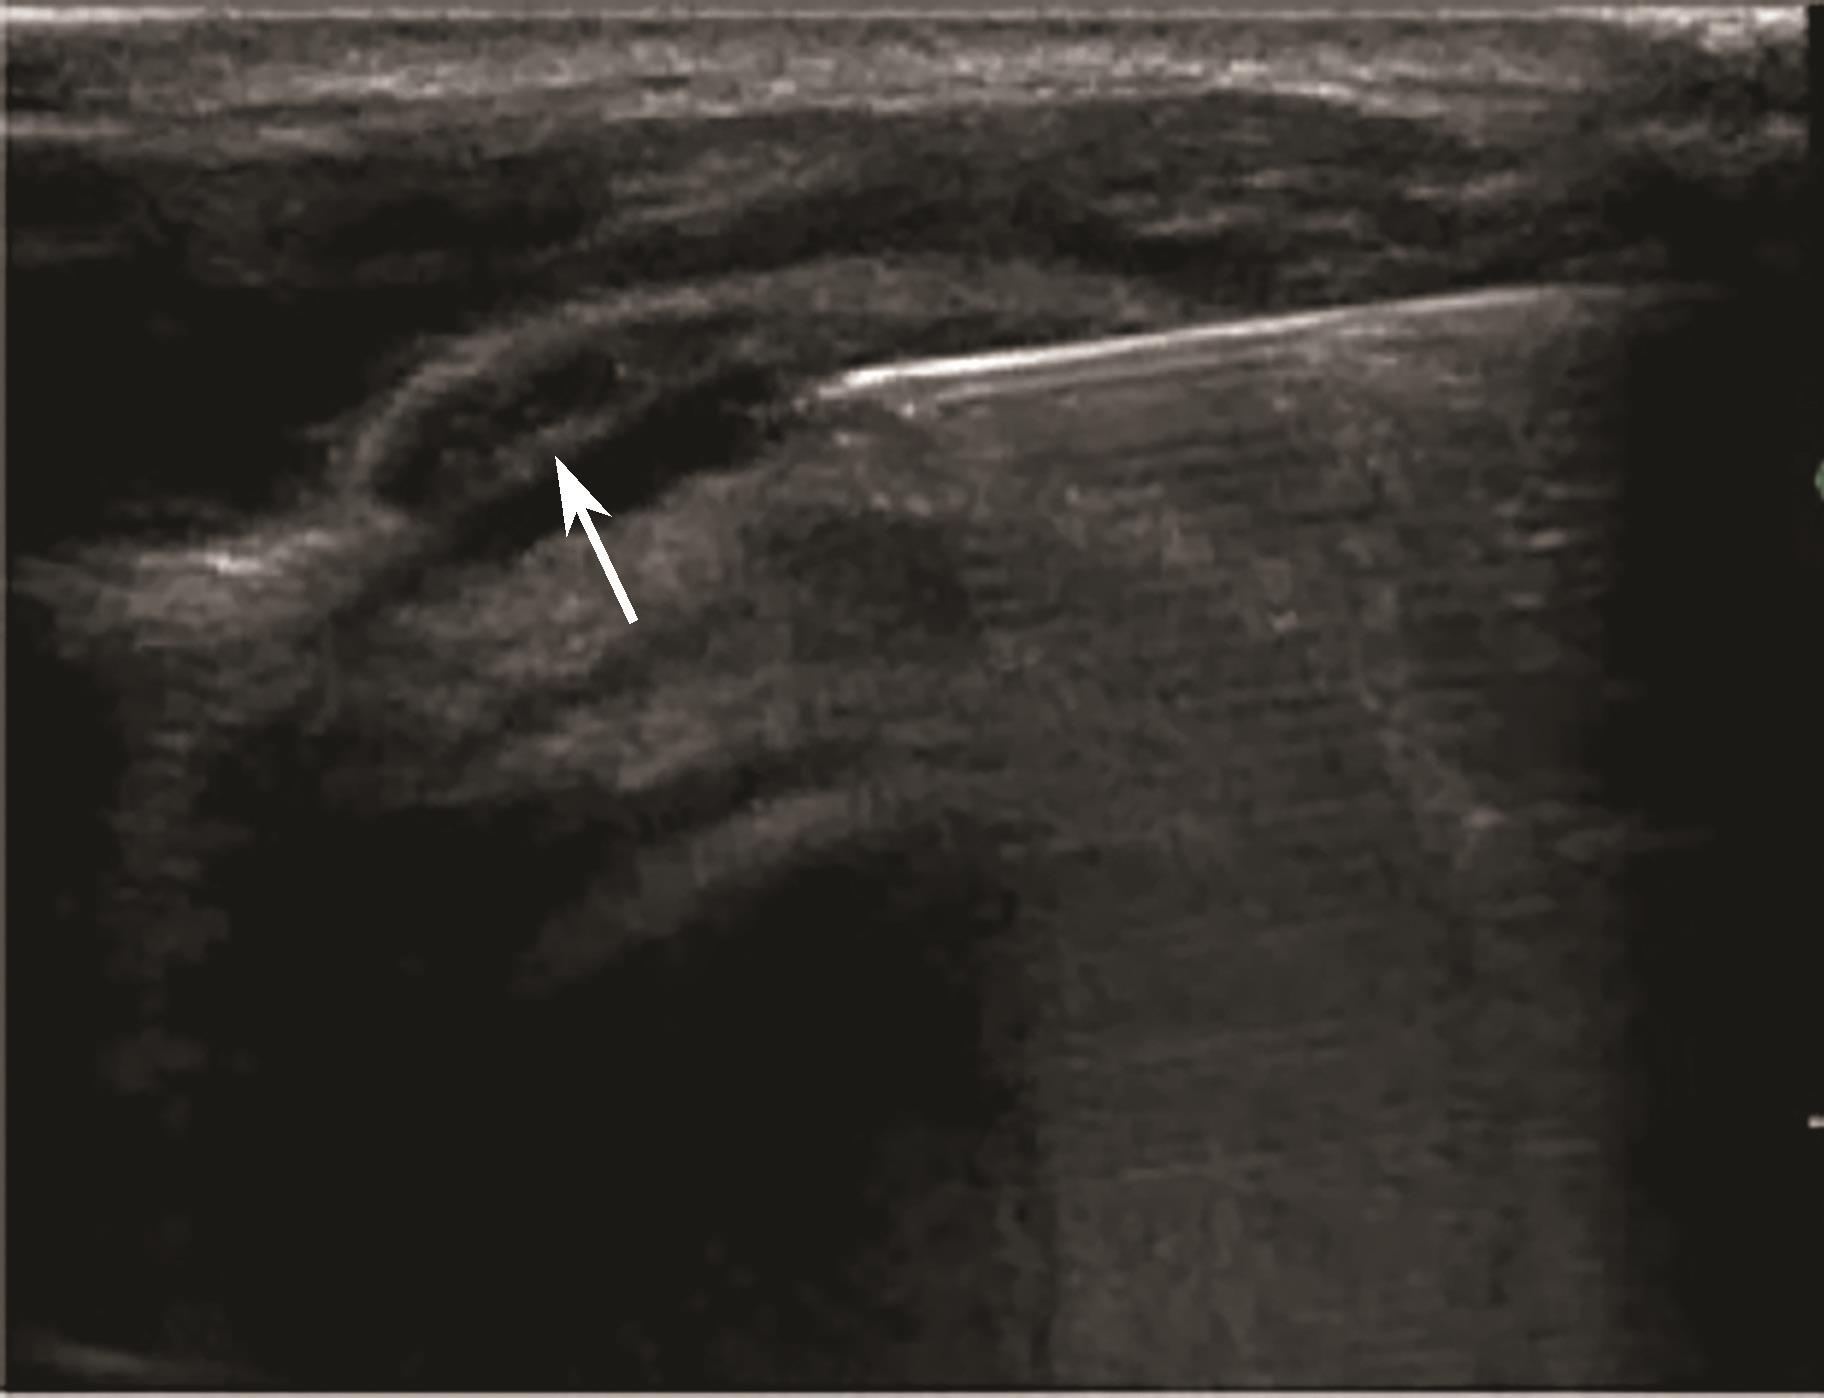

平面内进针法,从内向外或从外向内引导针尖进入滑囊后进行药物注射(图2-1-3、图 2-1-4)。

▲ 图2-1-3 超声引导下肩峰下-三角肌下滑囊注射操作图

▲ 图2-1-4 超声引导下肩峰下-三角肌下滑囊注射治疗超声图

箭头:穿刺针;星号:滑囊

2.当针尖进入滑囊后(图2-1-5),可推注少量药物,若推注顺利可观察到滑囊扩张及药物的弥散(图2-1-6),同时也表明针尖准确位于滑囊内,可继续推注混合药物3~5ml。若推注受阻,原因有可能是针尖在滑囊组织内,需重新调整针尖,也可能是滑囊内粘连明显所致,可加大力度,利用液体推注的压力松解粘连,松解后可见粘连带呈线状稍强回声(图2-1-7),也可在粘连远端重新选择部位注入药物,这类患者可能需要多次治疗才能达到较好的疗效。

▲ 图2-1-5 超声引导下肩峰下-三角肌下滑囊穿刺治疗超声图

箭头:显示穿刺针尖进入滑囊;星号:冈上肌腱;H:肱骨头